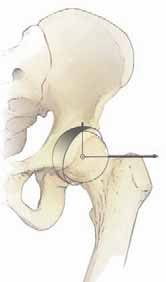

Chapter 24 Hip Arthroscopy: The Basics Marc Safran and Matthew A. Stanich DEFINITION The hip is increasingl…

Periacetabular Osteotomy DEFINITION According to the prefix peri (meaning “around”), a periacetabular osteoto…